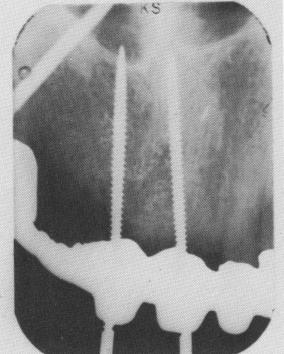

Fig. 7-22. Threaded pin implant. (Courtesy I. Lew.)

Pins. There are two types of pins, the French ones of Scialom and American modifications. The French pins are smooth-sided, with the pointed end to be driven into bone and the stress end bearing small ears to engage the various chucks (Fig. 7-20). 'The American models are similar, but their heads have more provisions for being secured to the acrylic core (Fig. 7-21). Some American models are also threaded (Fig. 7-22), but the threading provides little extra retention because of the pin's inherent narrowness.